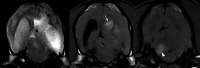

Results: No associations were found between clinicopathologic findings or survival and tumor type or grade. However, definitive treatments provided significantly (P = .03) improved median survival time (84 days; 95% confidence interval [CI], 45-190) compared to palliative treatment (26 days; 95% CI, 11-54). On magnetic resonance imaging (MRI), oligodendrogliomas were associated with smooth margins and T1-weighted hypointensity compared to astrocytomas (odds ratio [OR], 42.5; 95% CI, 2.42-744.97; P = .04; OR, 45.5; 95% CI, 5.78-333.33; P < .001, respectively) and undefined gliomas (OR, 84; 95% CI, 3.43-999.99; P = .02; OR, 32.3; 95% CI, 2.51-500.00; P = .008, respectively) and were more commonly in contact with the ventricles than astrocytomas (OR, 7.47; 95% CI, 1.03-53.95; P = .049). Tumor spread to neighboring brain structures was associated with high-grade glioma (OR, 6.02; 95% CI, 1.06-34.48; P = .04).

Conclusions and clinical importance: Dogs with gliomas have poor outcomes, but risk factors identified in survival analysis inform prognosis and the newly identified MRI characteristics could refine diagnosis of tumor type and grade.